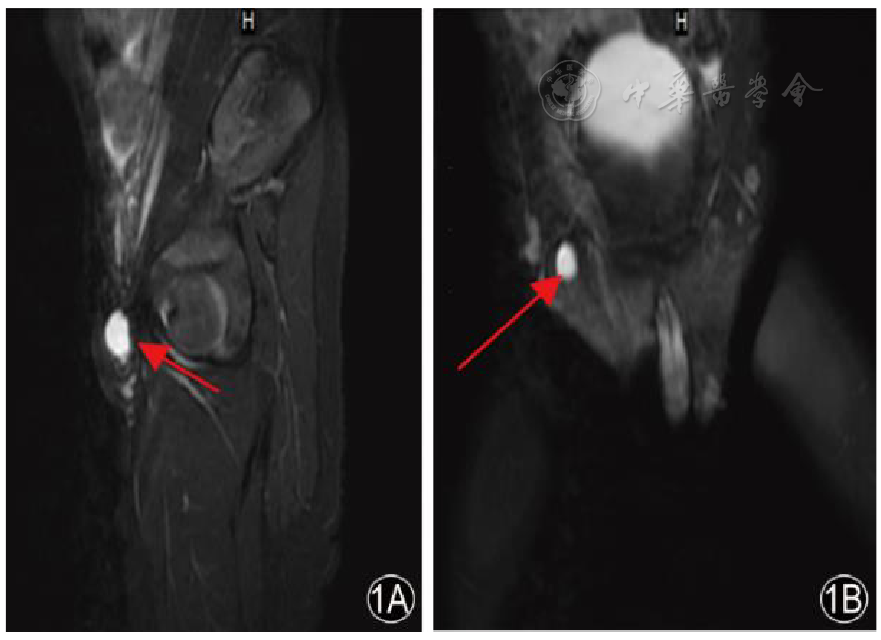

图1 半月线疝患儿腹部MRI检查注:箭头所示为皮下囊性包块,大小约1.2 cm×1.3 cm×1.6 cm;1A矢状位,1B冠状位。